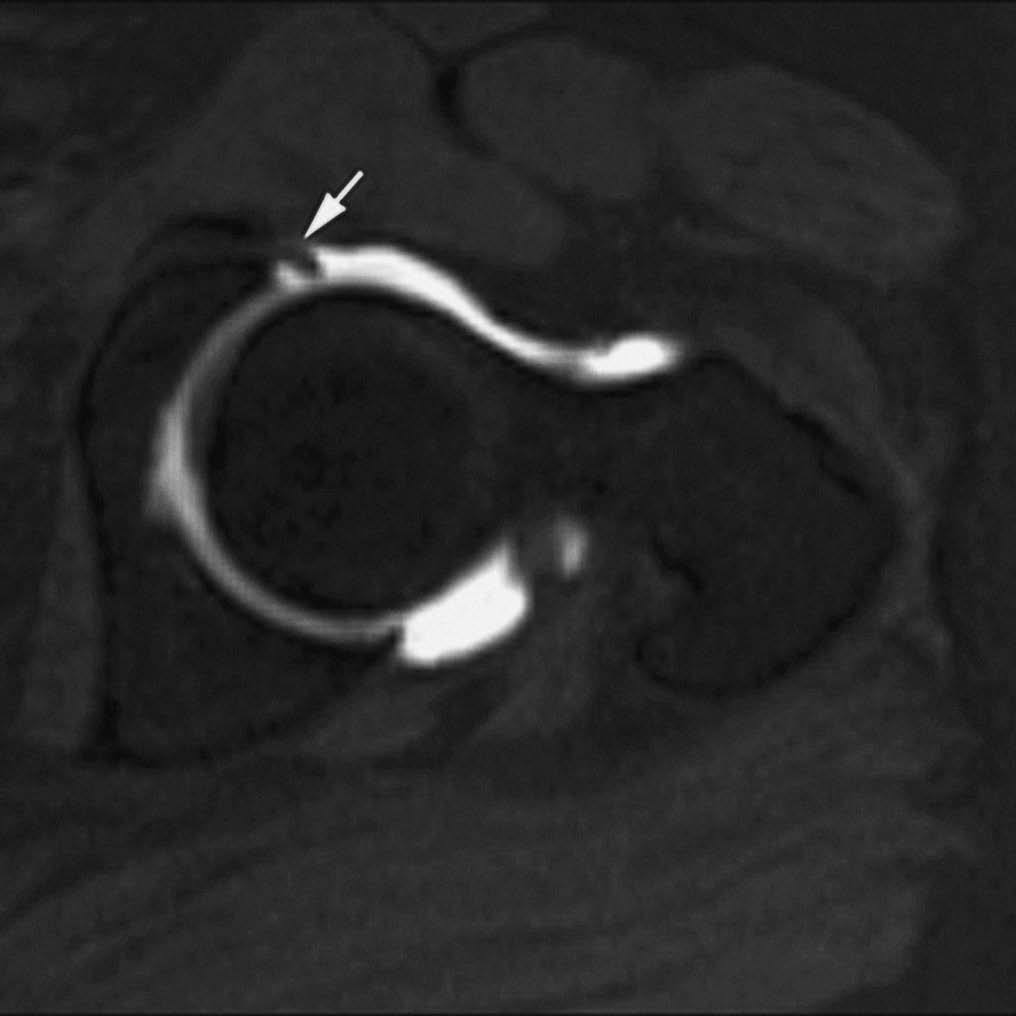

El síndrome de choque fémoro-acetabular está causado por el impacto repetido del cuello femoral sobre el borde del acetábulo debido a una alteración anatómica de la región proximal del fémur --disminución de la anteversión femoral y alteración de la relación normal entre los diámetros de la cabeza y el cuello femoral--. El tratamiento precoz de estas anomalías previene el desarrollo de coxartrosis. La RMA permite visualizar las alteraciones anatómicas del desarrollo, el estado del labrum acetabular, cartílago y cápsula articular (fig. 4)7-9.

Fig. 4.--Síndrome de choque fémoro-acetabular. Corte axial oblicuo de RMA potenciado en T1 con técnica de supresión grasa que muestra una deformidad en la transición cabeza-cuello femoral con edema focal (cabeza de flecha), formación de pequeño quiste sinovial (herniation pit), rotura del labrum antero-superior (flecha) y engrosamiento del ligamento ilio-femoral (asterisco).